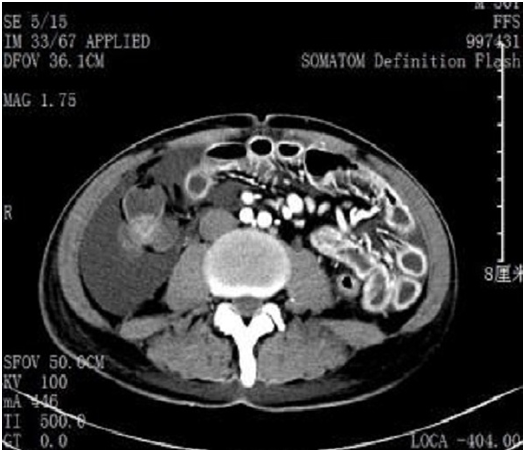

After admition, doctors in our center suspended his chemotherapy and started supportive treatment. However, the patient’s condition did not get better, the diarrhea frequency and white blood cell count increased gradually, at the same time, the albumin level and hemoglobin level decreased as a result of the consumption of severe diarrhea. Also, the patient suffered from a severe imbalance of water and electrolyte. Then we started to pay special attention to this case and try to find out the cause of his diarrhea. We gave the patient several times of stool culture and test of clostridium difficile toxin A&B, which revealed a negative result. A 5FU metabolism related genome test was also conducted to evaluate the sensitivity and tolerance of the patient for S1. The results revealed a genetic polymorphysm of gene TYMS, as well as a negative polymorphysm of gene DPD and MTHFR, which indicate a relatively good tolerance and sensitivity for the application of 5FU based chemotherapy (Figure 1). The CTscan conducted during the hospitalization periods revealed severe inflammation and edema on intestinal wall (Figure 2). The therapy was applied along with the serum evaluation and other examination. The supportive treatment includes fluid transfusion, management of water and electrolytic balance as well as albumin and blood transfusion when necessary. The pharmacological treatment is the combination of Glutamine, Celecoxib, Loperamide as well as Octreotide. The treating course is described in Figure 3.

Figure 2 The CT-scan revealed severe inflammation of intestine.